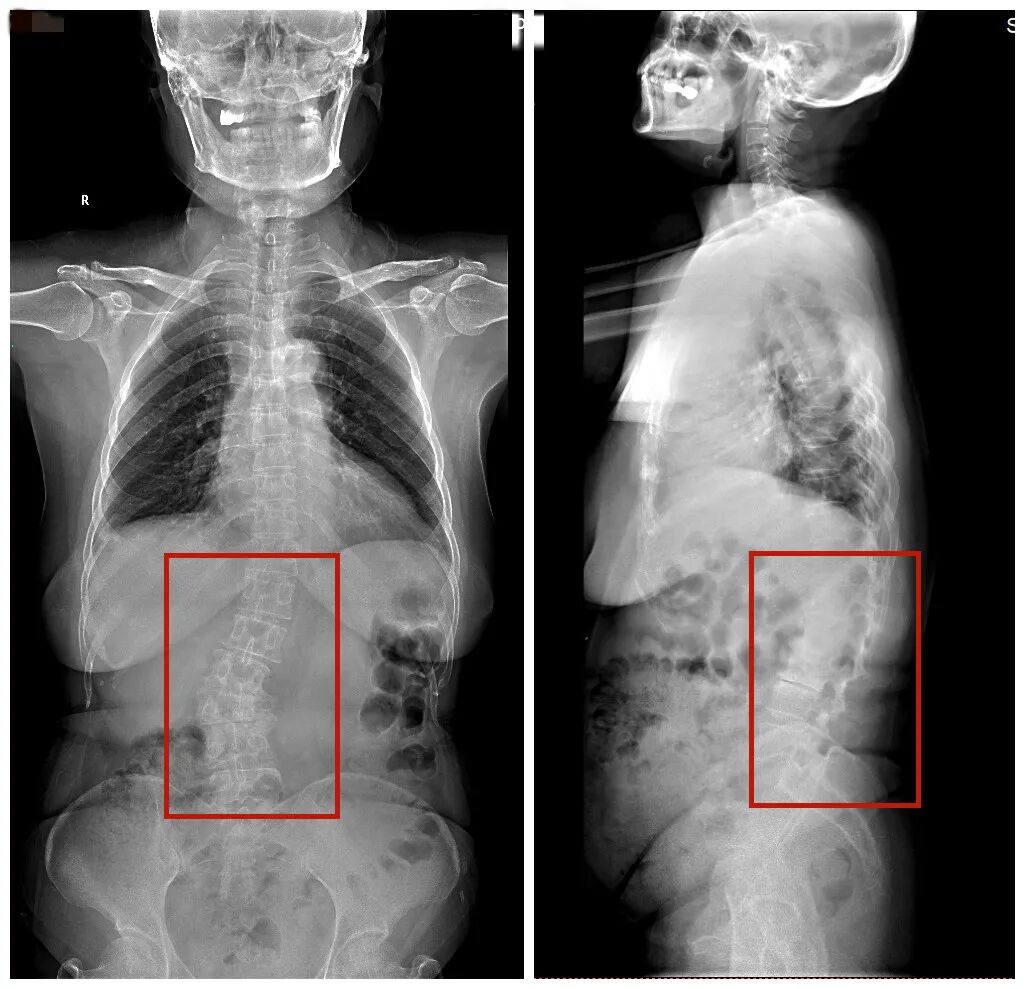

▲影像学检查提示退变性脊柱侧弯、

椎间盘突出、腰椎滑脱、腰椎管狭窄